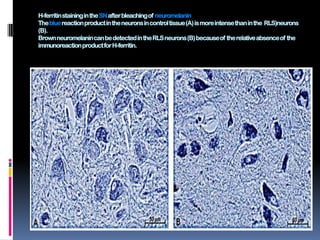

H-ferritin staining in the SN after bleaching of neuromelanin

The blue reaction product in the neurons in control tissue (A) is more intense than in the RLS)neurons

(B).

Brown neuromelanincan be detected in the RLS neurons (B) because of the relative absence of the

immunoreactionproduct for H-ferritin.